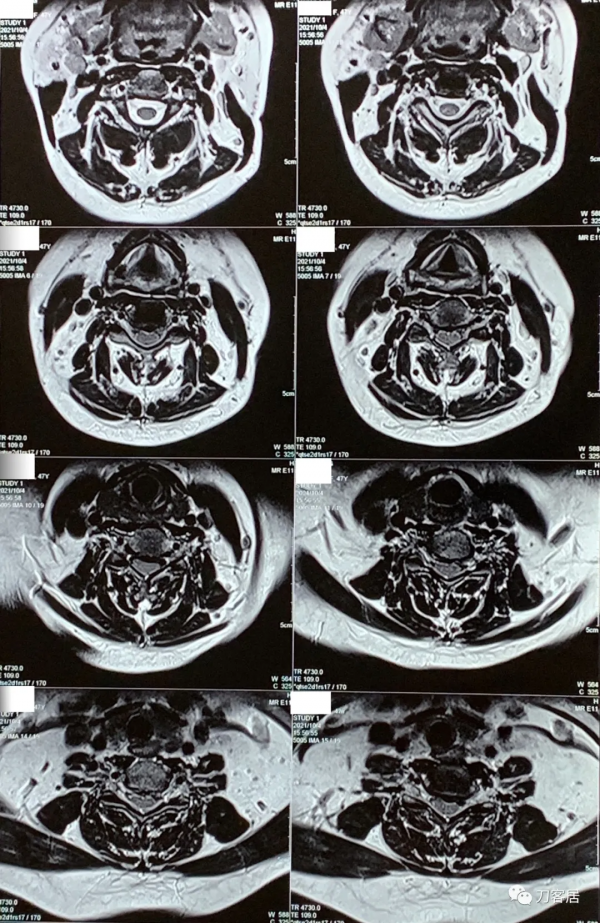

圖1. 20210913腰椎MRI矢狀面T2相,未見明確的椎間盤突出及椎管狹窄。

圖2. 20210913腰椎MRI矢狀面T1相,未見明確的椎間盤突出及椎管狹窄。

圖3. 20210913腰椎MRI橫截面,未見明確的椎間盤突出及椎管狹窄。

圖4. 20210913腰椎MRI橫截面,未見明確的椎間盤突出及椎管狹窄。